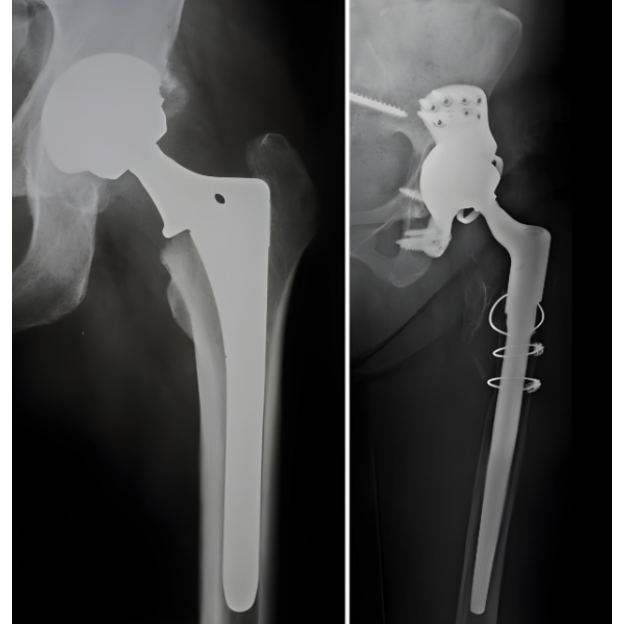

Revision Hip Replacement in Bangalore – Restoring Strength and Comfort

For patients who have undergone hip replacement in the past, complications like implant loosening, infection, or persistent pain may arise. In such cases, revision hip replacement offers a way to restore mobility and quality of life. At Kulkarni Orthopaedic Center Bangalore, the focus is on evaluating the reasons behind the failed hip replacement and providing a carefully planned revision surgery.

Revision procedures are more complex than primary hip replacements, requiring advanced surgical skills and careful assessment of bone quality, surrounding tissues, and implant stability. Modern techniques and high-quality prosthetic materials ensure long-lasting results, enabling patients to walk without discomfort. With experienced orthopaedic surgeons at the helm, patients receive comprehensive care before, during, and after the procedure.

This surgery is particularly beneficial for individuals facing recurring hip dislocations, chronic infections, or severe wear and tear of the implant. The goal is not just to replace the failed prosthesis but also to rebuild stability and strength in the joint.